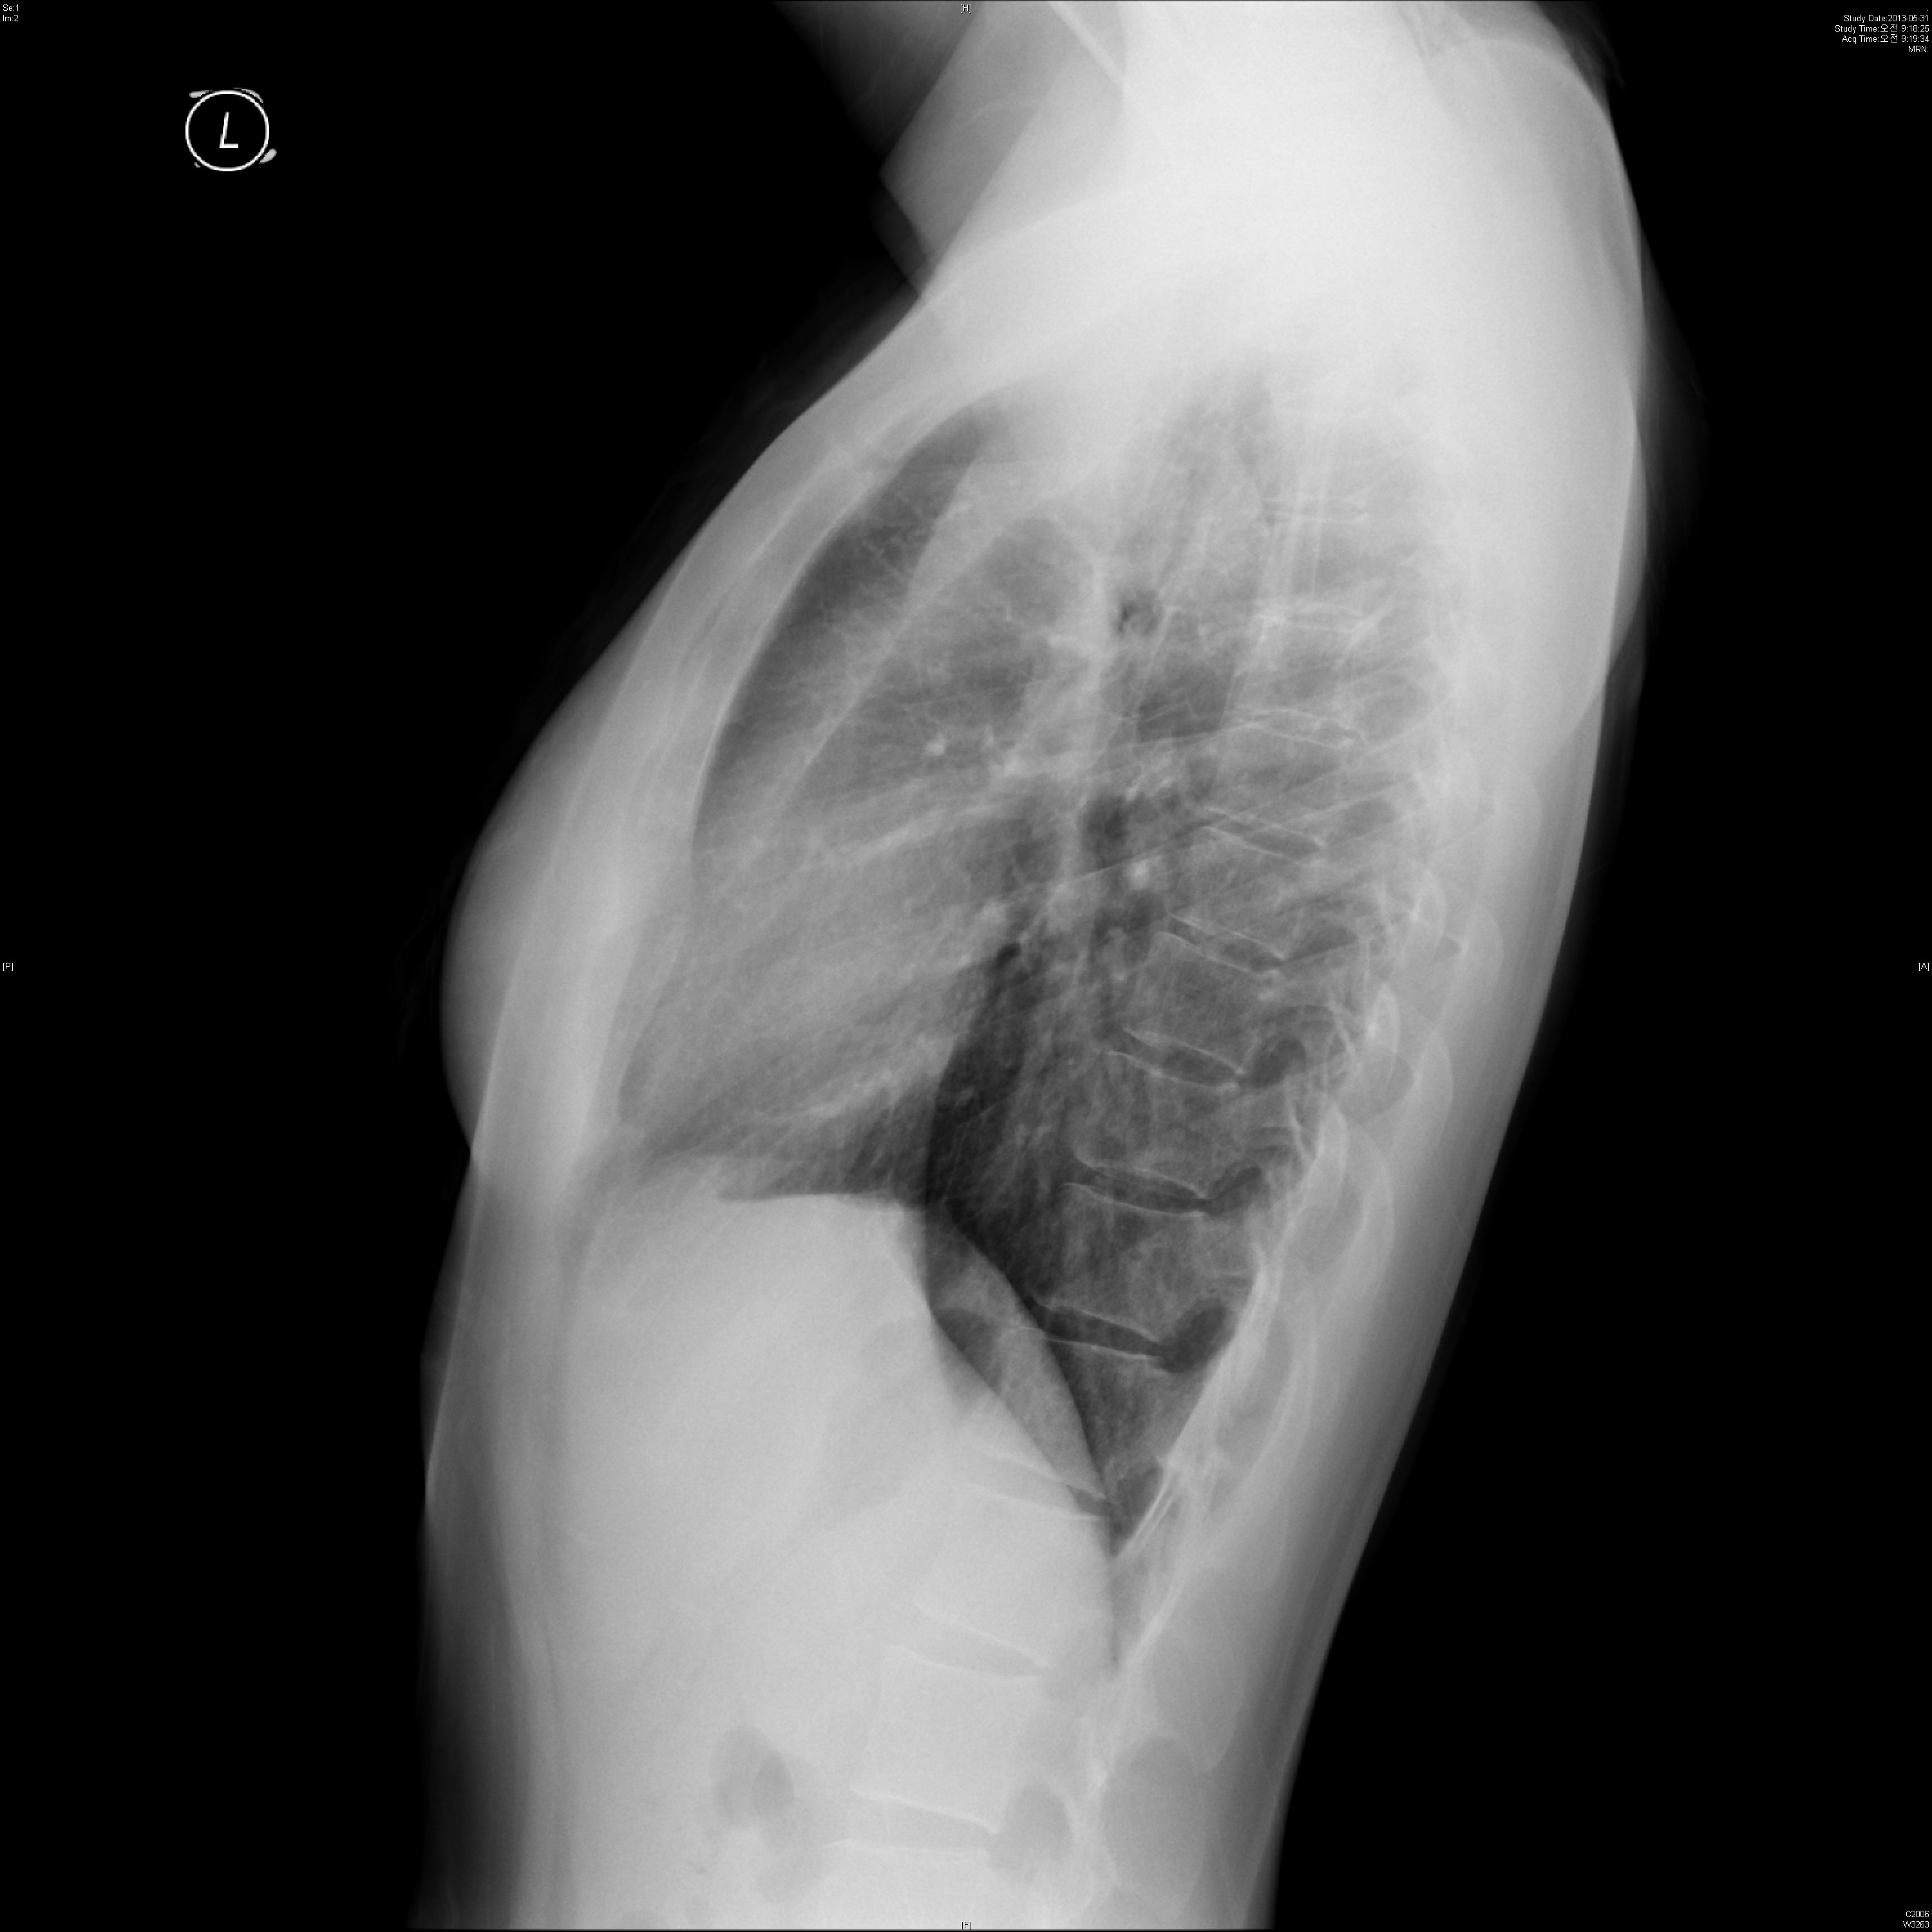

34¼¼ ¿©ÀÚÀÔ´Ï´Ù. TBÀÇ º´·ÂÀÌ ÀÖ½À´Ï´Ù.

´ÙÀ½ chest PA ¹× Lat(Lt)¿¡¼­ ¾Ë ¼ö ÀÖ´Â ÀÌ»óÀº ¹«¾ùÀϱî¿ä?